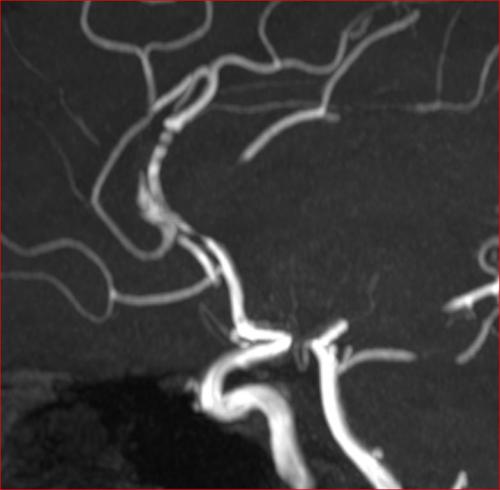

Aneurysma re. 7 mm Darstellung in einer DSA (digitalen Subtraktionsangiographie) links nur ein 2 mm „Baby-Aneurysma“ Im MRT war zuvor das linke Aneurysma aufgefallen, die Auflösung einer DSA ist technisch im MRT nicht erzielbar, beide A. liegen in der ACM Bifurkation jeweils, das re. Aneurysma wurde erfolgreich operiert, das linke Aneurysma wird kontrolliert.